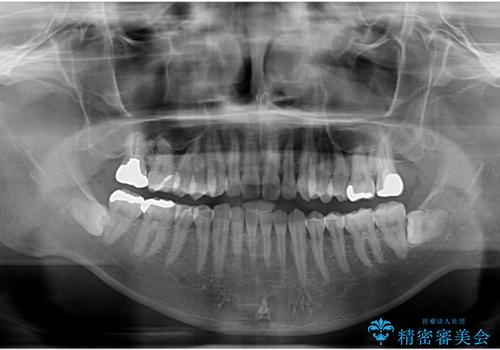

舌小帯を切りたい。

- 20代男性

- 滑舌が悪いとの事で来院。

当日に舌小帯の切除を行う事になりました。

- 舌小帯切除術 3.3万円費用は治療当時の料金となります